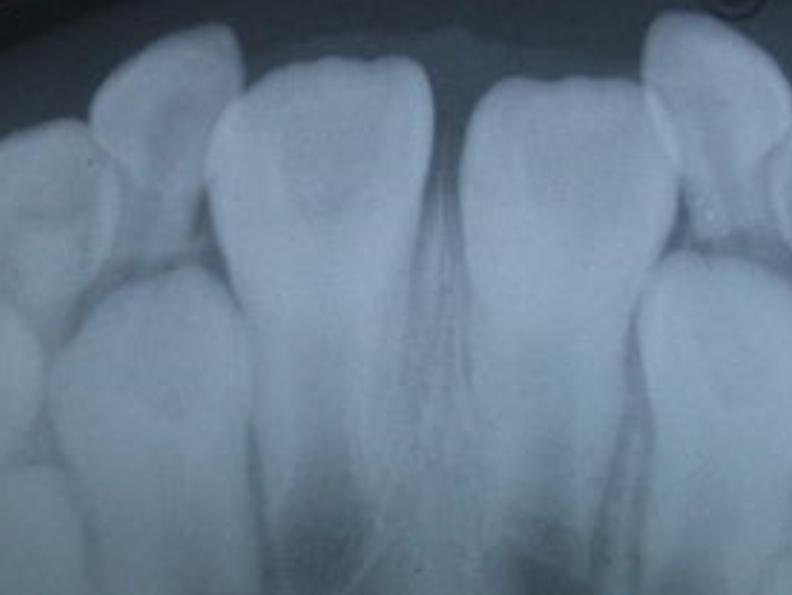

全国口腔流行病调查结果显示:12岁儿童恒牙龋病的患病率为28.9%,其中90%发生在第一磨牙。

这里要注意的是,宝宝的第一恒磨牙以后是不会更换的,一辈子长一次,所以要好好爱护。